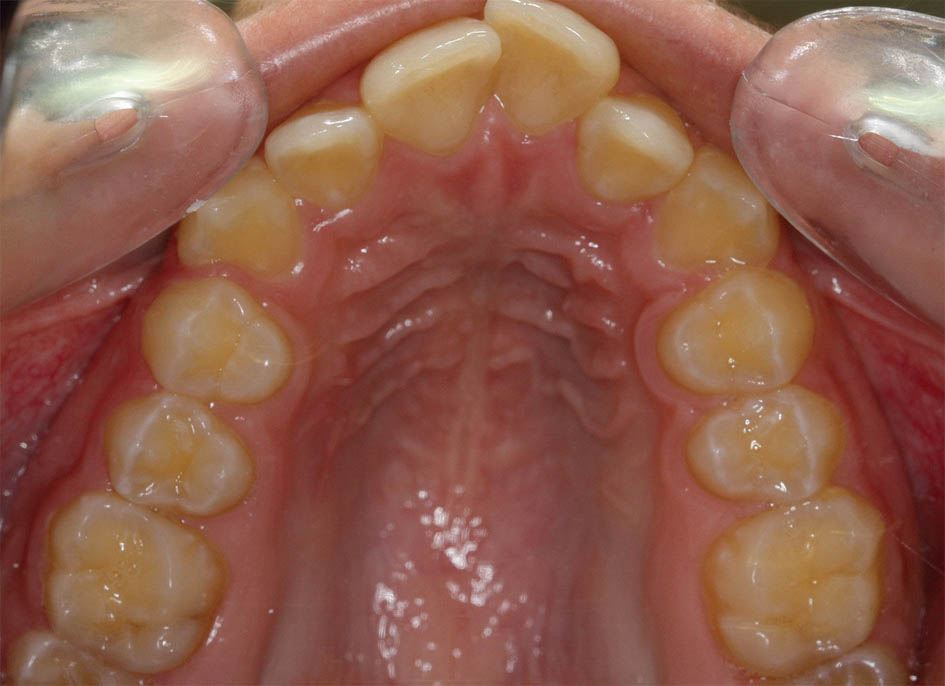

طی سالهای اخیر بعد از ارائه براکتهای Self Ligating تحقیقاتی انجام شده است. به دلیل اعمال نیروی ملایم در این سیستم براکتی، فعالیت سلولهای استخوان ساز بیشتر میشود. با افزایش عرض بین کانینها چون استخوان سازی هم رخ میدهد، شاهد حداقل برگشت درمانهای ارتودنسی هستیم (شکل 66-3 الی 69-3).

شکل 67-3: قوس بالا بعد از درمان با براکتهای self ligating